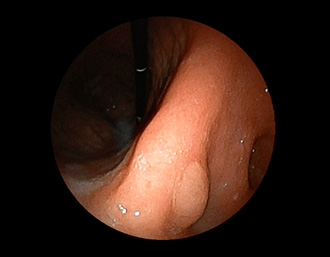

症例1:胃潰瘍(37才、男性)

①胃潰瘍(Stage A1)

健診:胃レントゲン検査で、胃角部ニッシェを指摘され当院受診。

胃角部小弯に、深くて大きな、大きさ約10mmの胃潰瘍(stage 1)

があり、潰瘍底は一部白苔はみ出しを認める。エソメプラゾールマグネシウム水和物投薬で治療開始しました。

(通常画像)